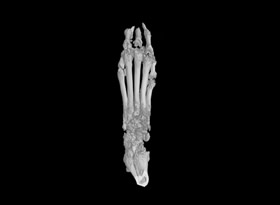

用于骨質疏松和關節(jié)炎動物模型潛伏期的骨結構和密度改變的研究。MicroCT是目前研究骨立體結構、容量和微結構細微改變較好方法。

1.掃描重構:常規(guī)樣本,一個視野可以掃的樣本,按以上報價。對于一些特殊樣本或較大樣本,可能需要多個視野掃,費用按相應的視野數(shù)計算,比如大鼠爪子至少需要3個視野。

2.數(shù)據(jù)分析:如果需要做多個部位分析,需要按部位數(shù)量收費,骨密度(BMD)單獨收費。